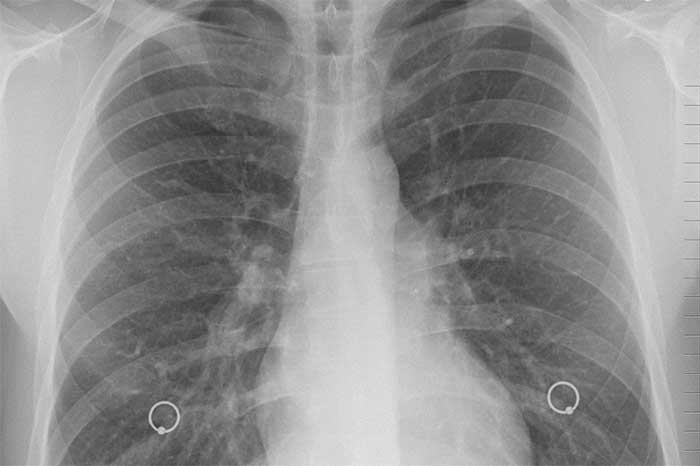

Sin embargo, tres días después de la operación, la receptora tuvo fiebre; su presión arterial bajó y su respiración se volvió dificultosa. Las radiografías mostraron signos de infección pulmonar.

A medida que su condición empeoraba, la paciente desarrolló un shock séptico y problemas de función cardíaca. Los médicos decidieron realizar la prueba para SARS-CoV-2, dijo Kaul. Las muestras de sus nuevos pulmones dieron positivo.